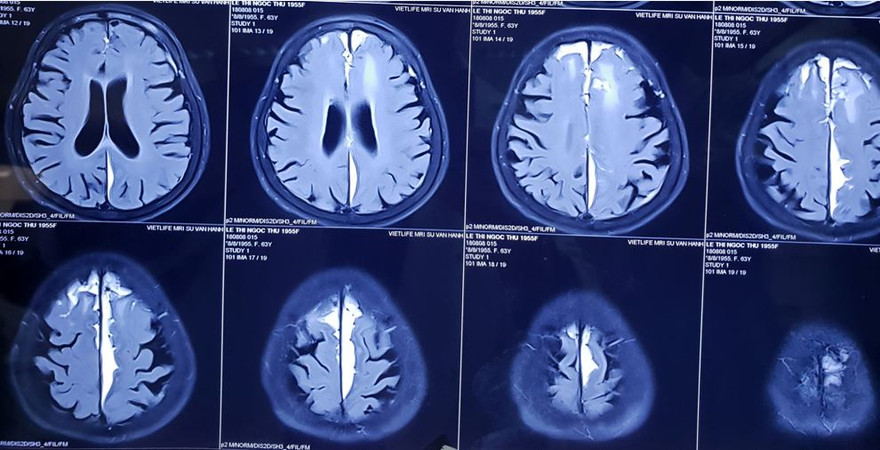

Qua kiểm tra, các bác sĩ ghi nhận bệnh nhân tiếp xúc được nhưng có biểu hiện liệt chân phải hoàn toàn, sức cơ 0/5 và có tiền căn đái tháo đường type 2 - tăng huyết áp. Kết quả CT scan sọ não cho thấy, bệnh nhân bị dập não trán 2 bên, máu tụ dưới màng cứng khe liên bán cầu bên trái cấp tính chèn ép vùng vỏ não cạnh trung tâm (paracentral lobule), điều này lý giải việc chân phải của bệnh nhân liệt hoàn toàn.

Bước đầu, các bác sĩ khoa Ngoại Thần kinh Bệnh viện Nhân Dân 115 quyết định điều trị bảo tồn cho bệnh nhân, sau 10 ngày chụp CT scan kiểm tra cho thấy dập não trán hai bên đã tự hấp thu, hội chứng thùy trán có cải thiện, bệnh nhân vui vẻ trở lại, nói chuyện bình thường. Tuy nhiên, chân phải của bệnh nhân vẫn liệt, sức cơ 0/5, trên MRI não cho thấy máu tụ khe liên bán cầu bên trái chuyển sang giai đoạn bán cấp và mãn tính. Trước tình hình này, các bác sĩ nhận định, đây là thời điểm tốt nhất để phẫu thuật cho bệnh nhân, vì nếu phẫu thuật lúc này thì chỉ cần gây tê tại chỗ, thời gian phẫu thuật ngắn và hiệu quả cải thiện vận động chân sẽ thấy được ngay trong lúc phẫu thuật